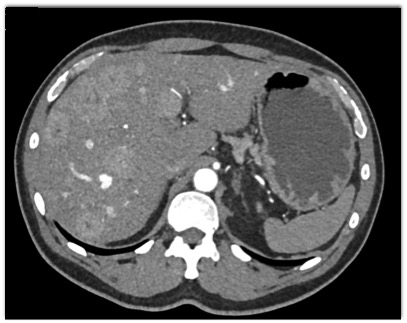

The most likely diagnosis in this case is?

multifocal hepatoma

metastatic renal cell carcinoma

carcinoid tumor

GIST tumor